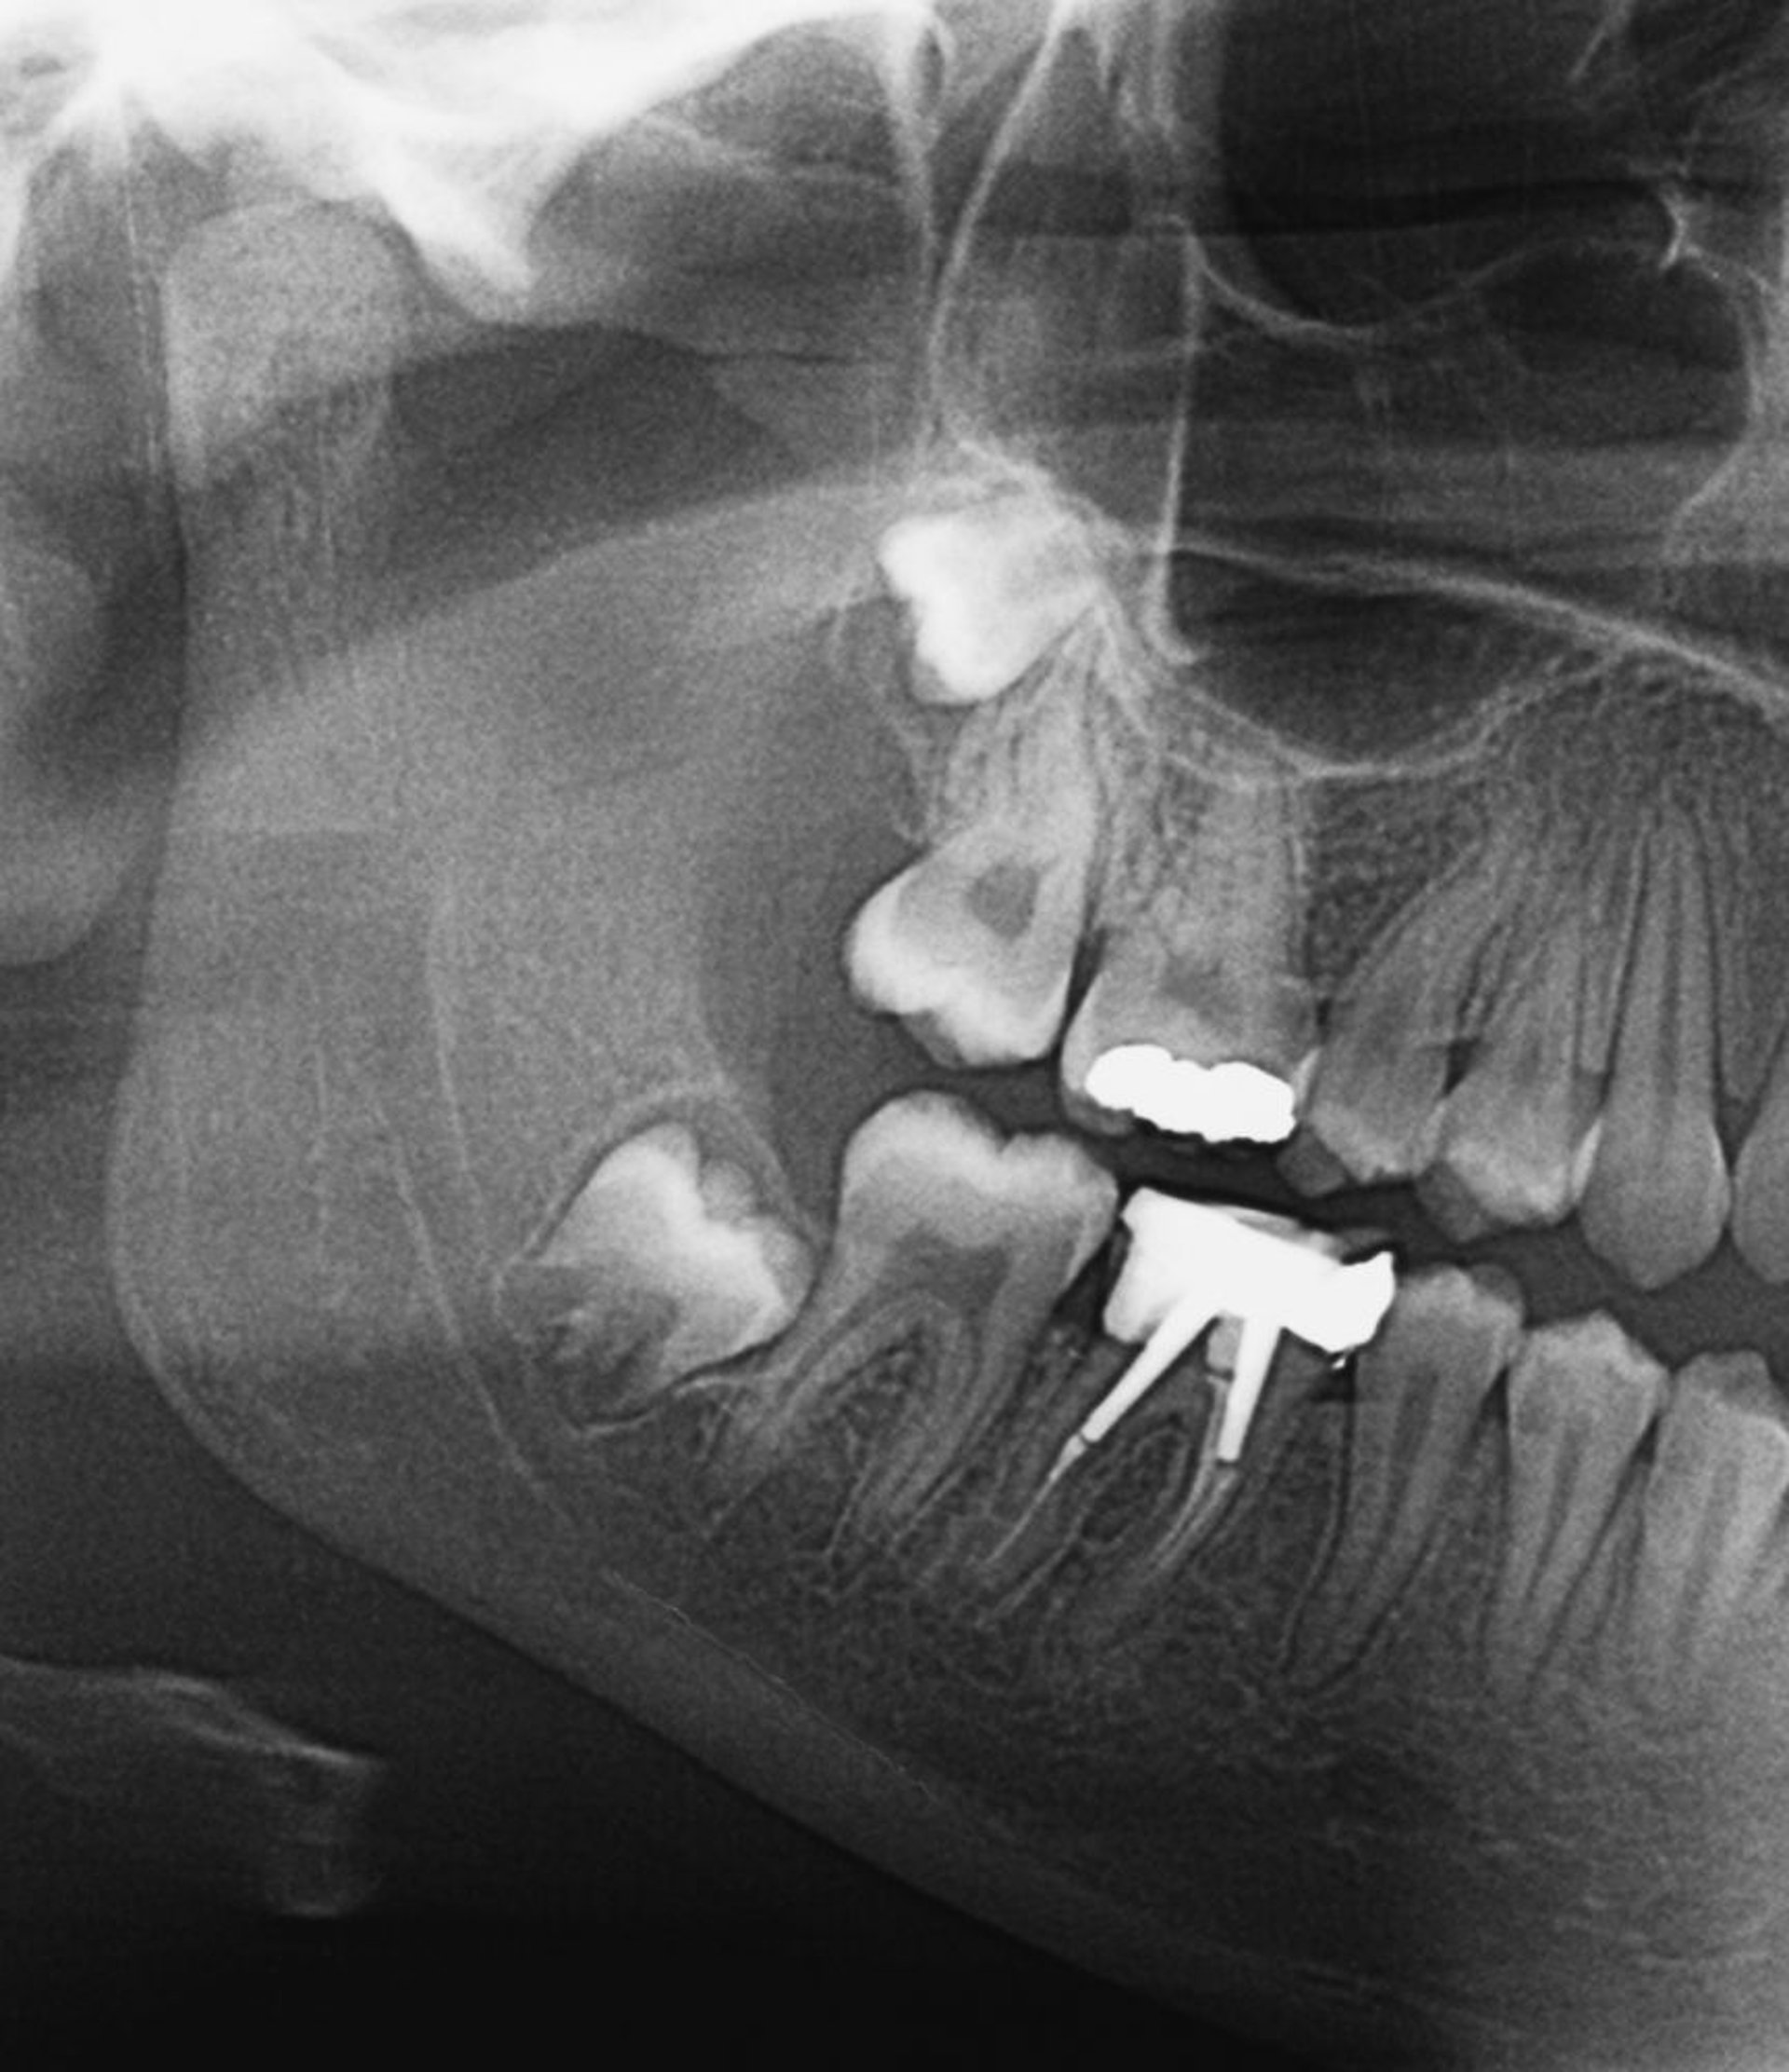

埋伏智歯

このX線像には,埋伏智歯が写っている。智歯が萌出する際,または不完全埋伏である場合には,智歯周囲炎が生じることがある。